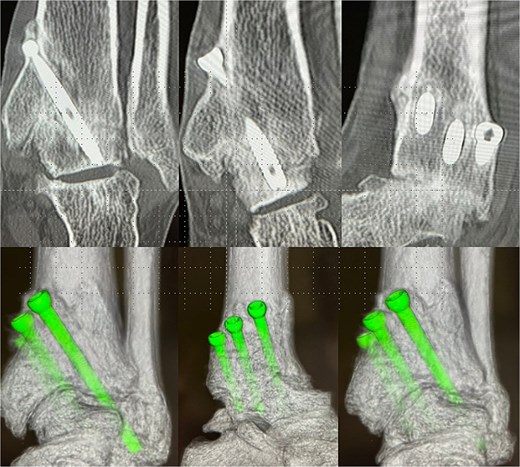

Preoperative radiographs and computed tomography (CT) demonstrated complete loss of the tibiotalar joint space, talar subluxation, and extensive osteophyte formation consistent with end-stage post-traumatic osteoarthritis (Figs 1 and 2). After informed consent and institutional review board approval (IRB number #20251001), the patient underwent arthroscopic ankle arthrodesis.

Preoperative radiological imaging: CT finding. The articular surface is completely collapsed and obliterated (1: white arrowhead). The talus is positioned in a subluxated state, and multiple osteophytes are observed on the medial, lateral, and posterior aspects (2–4: black arrowhead / circle with dotted outline). Both radiographs and CT images demonstrated end-stage osteoarthritis of the ankle, characterized by complete collapse of the articular surface and multiple osteophytes along the anterior, lateral, and posterior aspects of the joint (circle with dotted outline).